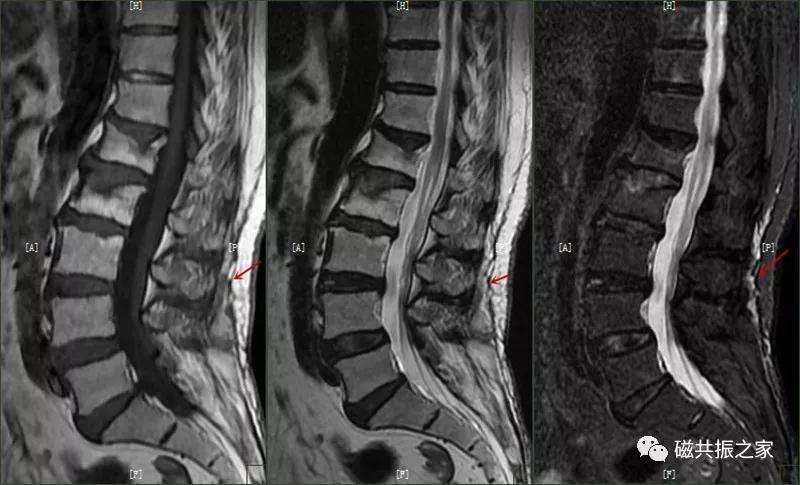

12.休门病/许莫尔结节/椎体边缘骨

休门病(Scheuermann,sdisease),主要由椎板骨软骨炎引起骨生长障碍,常见于青少年胸腰椎脊柱病变。

主要表现:椎体发育异常,椎体楔形改变,高度变低,前后径正常,常形成脊柱后凸畸形。

在矢状面上T1WI和T2WI显示各椎体楔形变,椎体高度减小,椎间隙变窄。椎体后1/3区呈多发性小骨质凹陷的Schmorl结节改变,髓核组织突入其中,边缘清楚,常呈上下对称分布,青少年病变周围可见长T1长T2信号,提示骨小梁水肿。

许莫尔结节(Schmorl,snodes),是休门病的一个病例征象。1930年Schmorl对照检查8000例尸检和X线发现椎体生长板发育不完善,或后天外伤致椎间盘突入椎体骨松质内,形成椎体压迹,是休门病的主要征象之一。除休门病外,其他的原因引起的生长板破坏,也可能产生Schmorl结节样改变。

矢状面显示椎体上或下椎间盘面异常信号,常呈长T,长T2信号,见髓核信号突入椎体内,常伴椎间隙变窄,常见于L3~S1椎体。